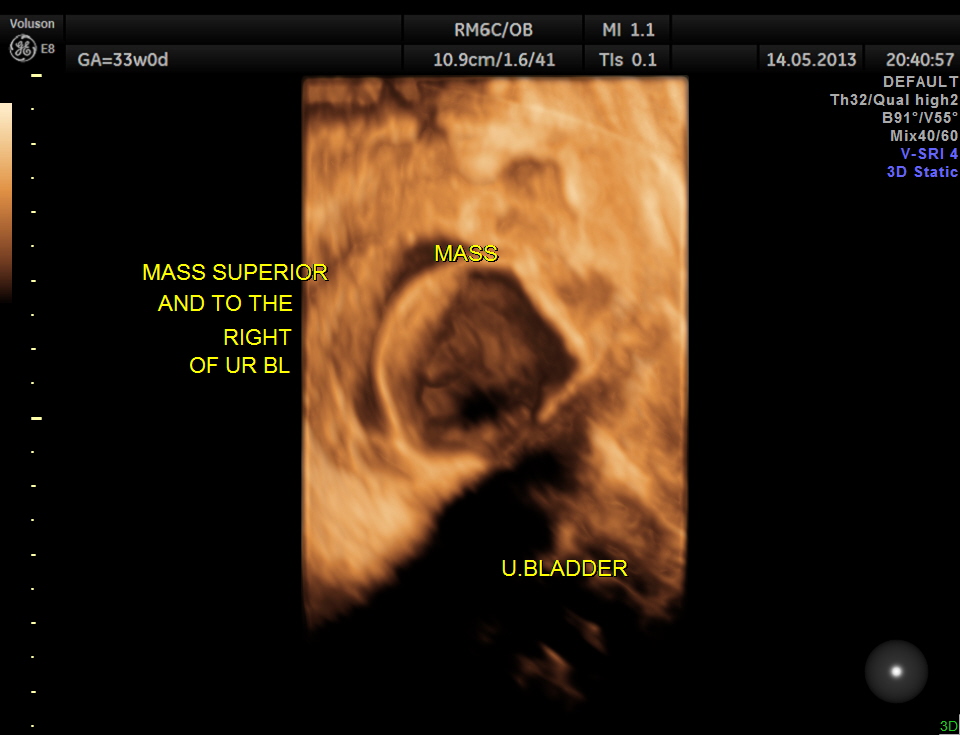

The lower abdomen showed a predominantly cystic mass with septations and internal echoes .

This was distinct from the urinary bladder and the kidneys. Both the kidneys showed mild pelviectasis.

The diagnosis offered was probable ovarian cyst with a D.D. of mesenteric cyst